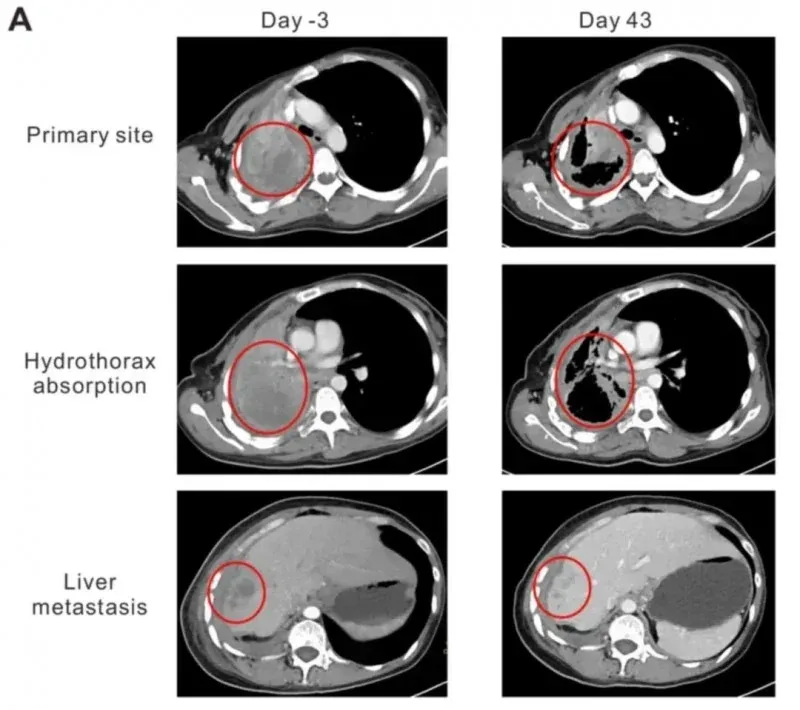

结果显示:2例分别接受3次、2次细胞输注的患者获得临床反应:按RECIST1.1标准,1例治疗后近3个月维持病情稳定(SD);1例(患者2)治疗后4个月达到部分缓解(PR),且疗效与安全性表现尤为突出。

值得一提的是,其中一例晚期肺腺癌女性(患者2),在接受治疗后不仅达到部分缓解(PR),且无明显毒性,生活质量与临床症状显著改善:卡氏功能状态评分(KPS)从50分提升至90分,咯血、胸痛症状明显减轻,胸腔积液完全吸收、肺组织复张。同时,其血清中细胞因子IFN-γ水平在细胞输注后第二周达峰值(首次输注后48.92pg/ml,二次输注后47.63pg/ml),随后逐渐回落。更直观的是肿瘤缩小数据:治疗第43天的CT显示,肺部原发灶从95×86×54mm缩小至64×44×54mm,肝部转移灶从19.8×19.6×20mm缩减至10×10×10mm。